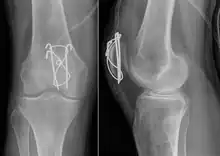

Comminuted fracture of patella

Most patella fractures are transverse or comminuted, hence the quadriceps mechanism is disrupted and they are treated by a combination of wires in a tension band construct. This unites the fractured bones, reconstructing the straightening mechanism of the leg.[5][6]

If the patella is broken in several places, that is comminuted, then traditionally a patellectomy (removal of the whole patella) is performed in order to reconstruct the extensor mechanism and prevent the onset of an extension lag at the knee joint, resulting in instability.[5][10][11] Some surgeons however would rather opt for internal fixation.[10] A partial patellectomy is removal of only a portion of the patella, and may be carried out if at least 60% of the patella can be maintained.[10][6]